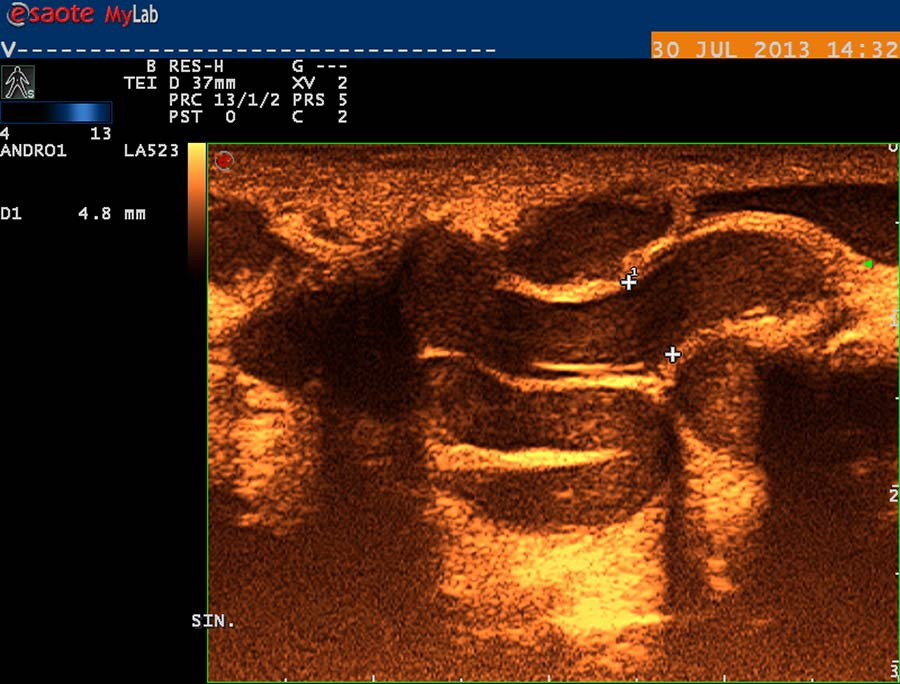

USG diagnostika vyžaduje odpovídající vybavení (obr. 12), zkušenosti a dostatek času. Vyšetření USG provádíme po termografickém vyšetření, na lůžku vyhřívaném na 30 st. Celsia, ultrasonografický gel zahříváme ve vodní lázni na teplotu 35 stupňů. Chladová kontrakce musculus cremaster vede k falešně negativním nálezům. Základní projekcí je koronární sken varlete (obr. 14) následovaný volumometrií ve dvou rovinách (obr. 15). Již na těchto skenech varlete je patrné rozšíření intratestikulárních cév, lépe je však viditelné při harmonickém („tissue enhancement imaging – TEI“) zobrazení (obr. 16, 17), a při barevném Dopplerovském zobrazení (Power Doppler) s TEI (obr. 18) s měřením šíře stěny a lumen žíly. Objemné dilatované žíly pampiniformního plexu jsou velmi dobře patrné na kolorizovaném TEI zobrazení (obr. 19), kde je možné zachytit pohyb venózní krve v souvislosti s dechem, intraabdominálním (IAP) a intrathorakálním tlakem. Informaci o atrofizaci tkáně získáme ze záznamu deformace kontury tunica albuginea podložkou, kterou je měkká buničina vložená pod skrotum (obr. 20, obr. 21 s volumometrií). Triplexní Dopplerovský záznam umožní hodnotit délku žilního refluxu a rychlost proudu refluktující krve v inspiriu, reflux při zvýšení intraabdominálního tlaku (obr. 22,23). Duplexní Dopplerovský záznam při harmonickém zobrazení s kolorizací zachycuje senzitivně změnu rychlosti proudění při refluxu v inspiriu s navazujícím zvýšením rychlosti při IAP (obr 25). Významná je možnost zachycení refluxu při klidném dýchání (respirační reflux, obr. 26).

obr. 16

obr. 17